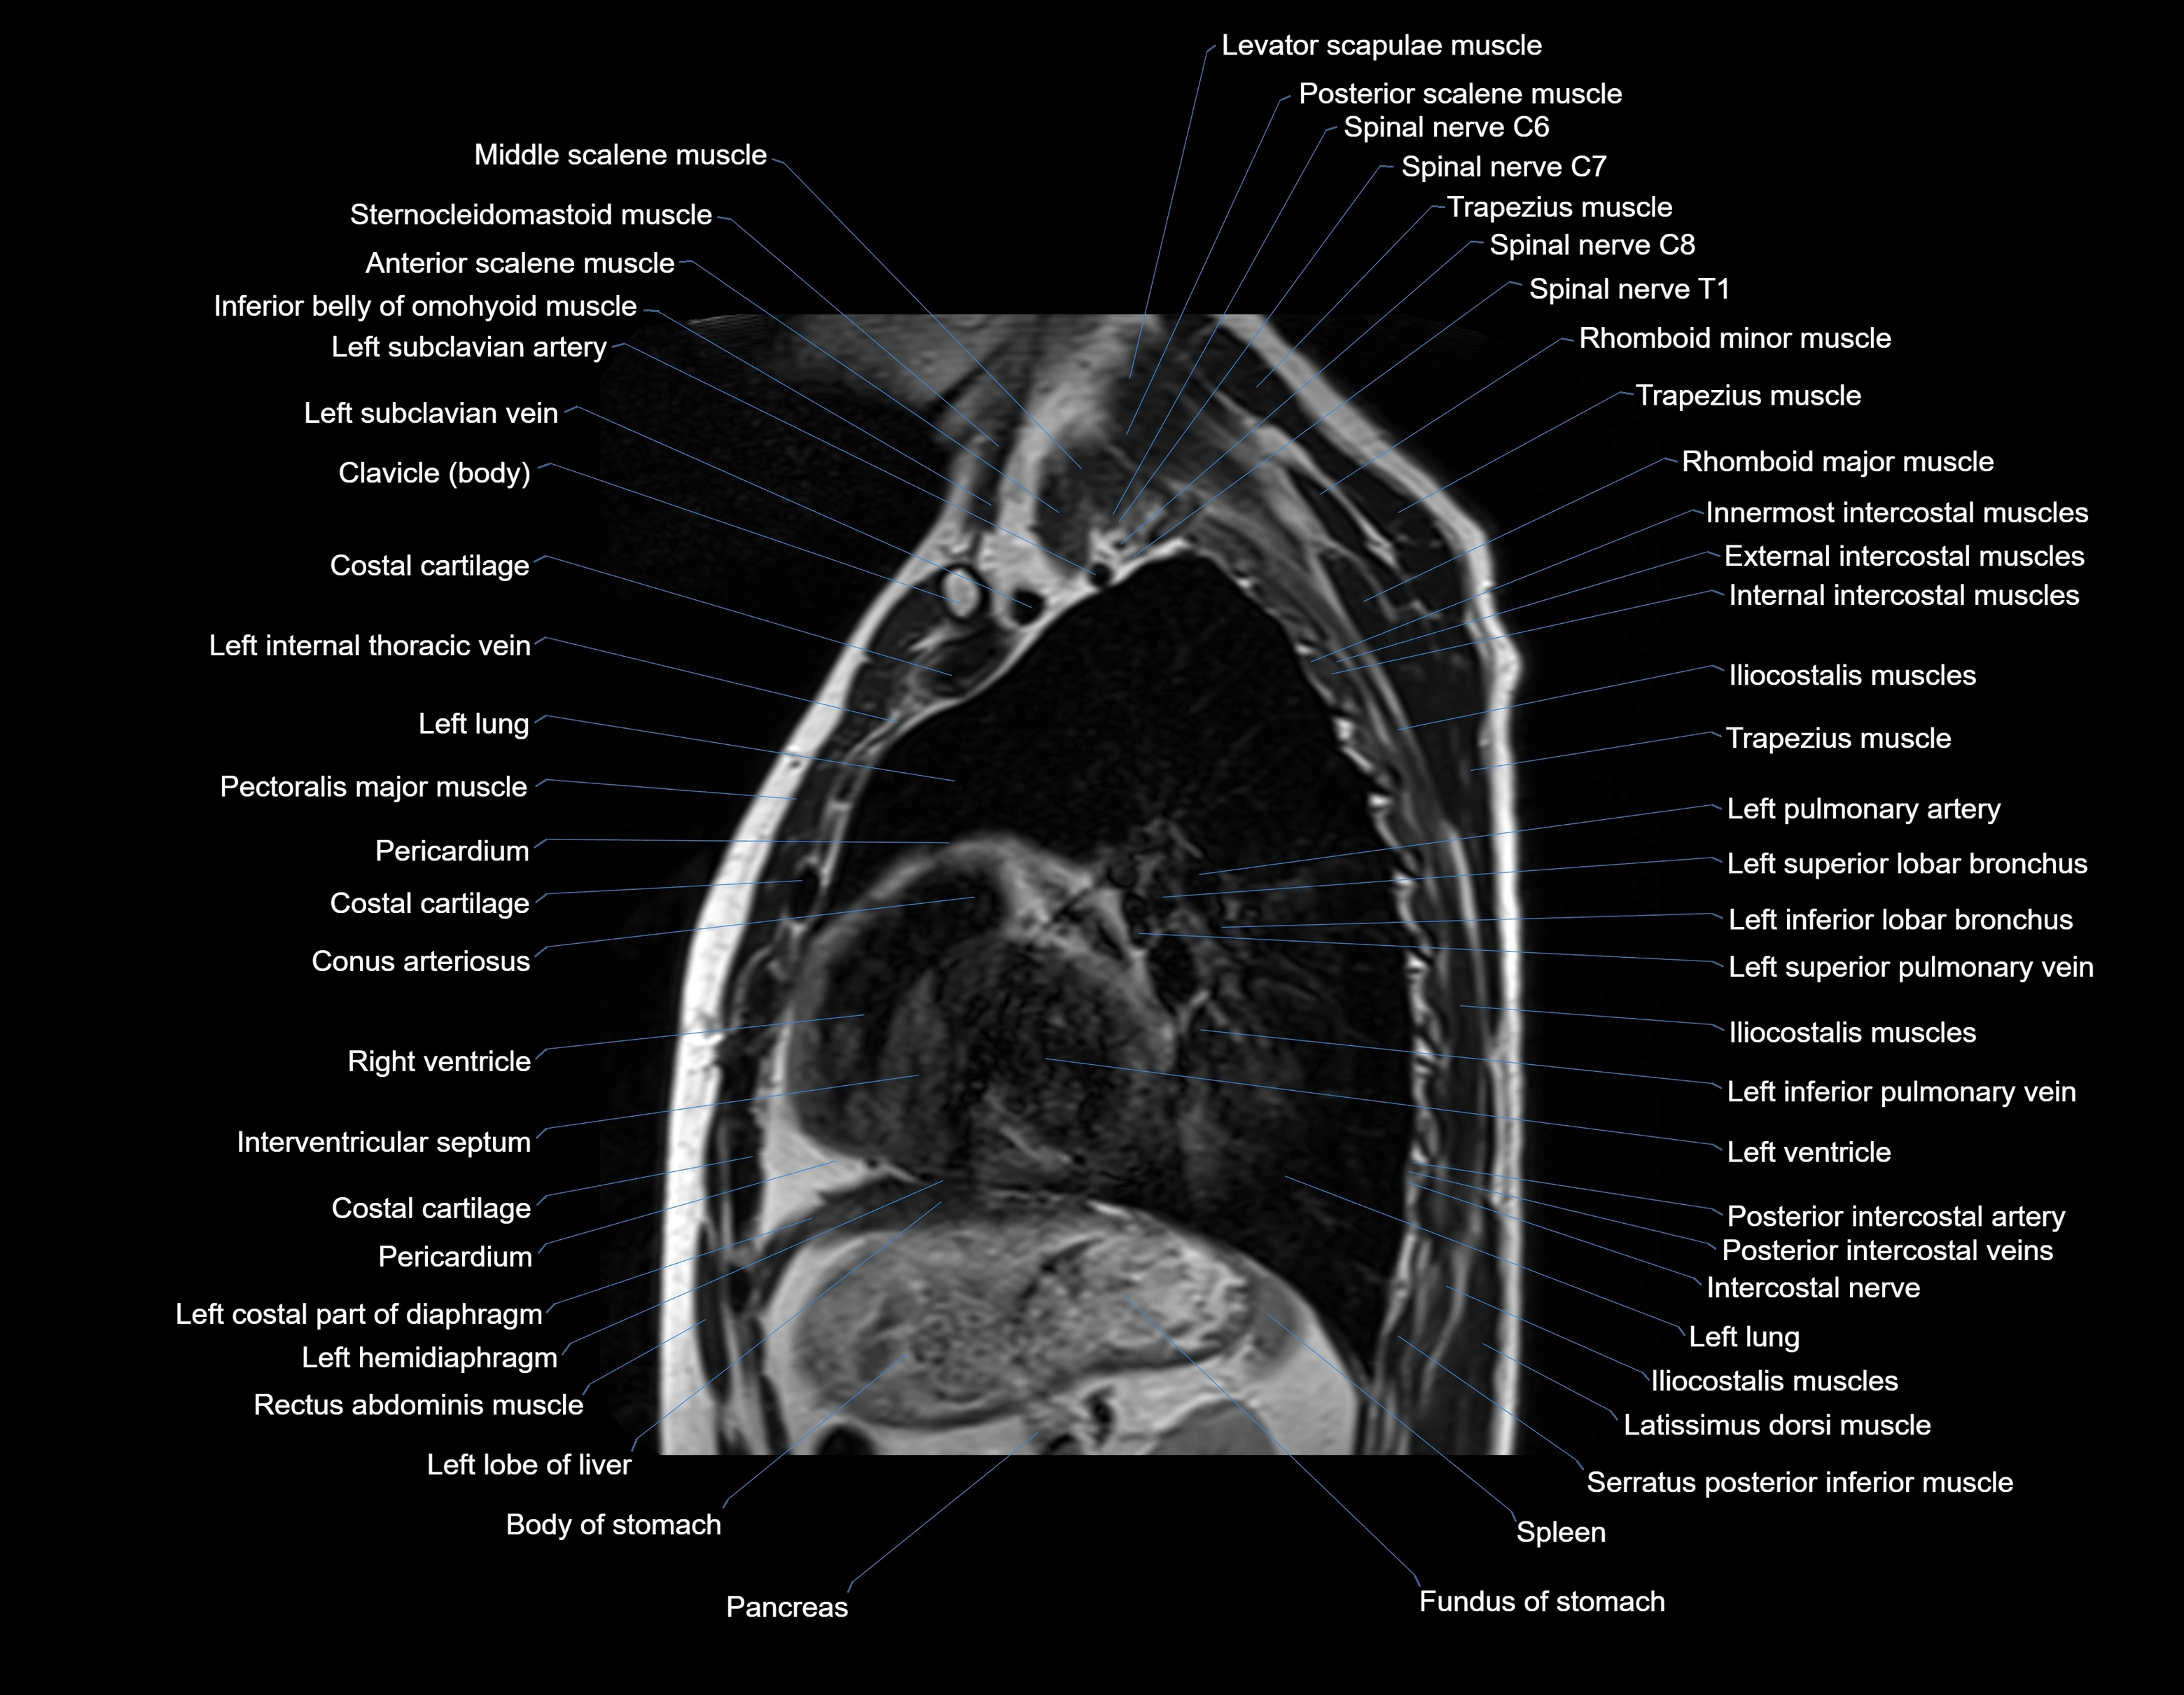

- T (Thoracic spine)